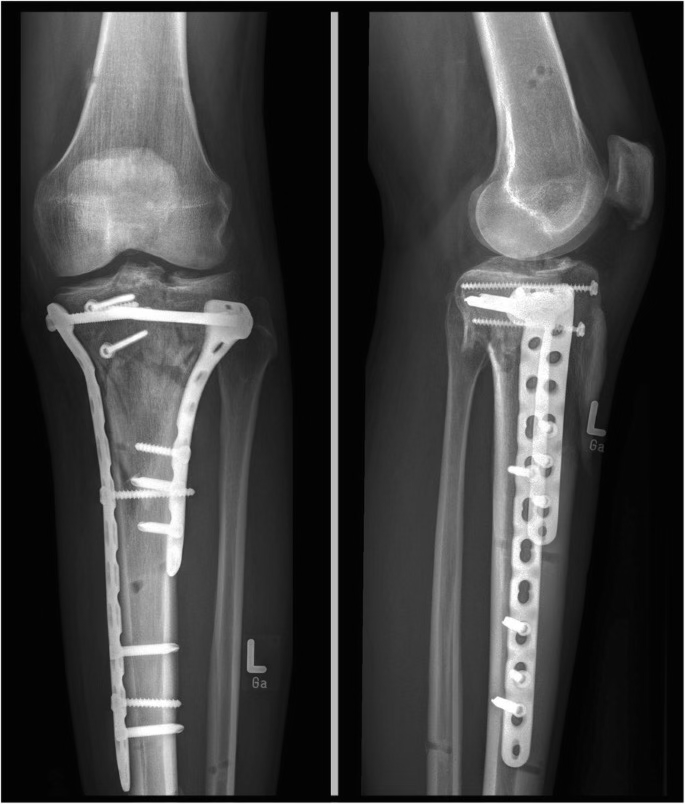

He is a Navy veteran who loves to play music and take care of his dog River. On the 27th of April, Colin was hit by a car while pumping gas. His forehead was split open, teeth broken, the nerves in his left arm were ripped from his spine, and his left leg was shattered completely. After a very long and painful recovery, Colin has regained his ability to walk and has most of the use of his left arm.